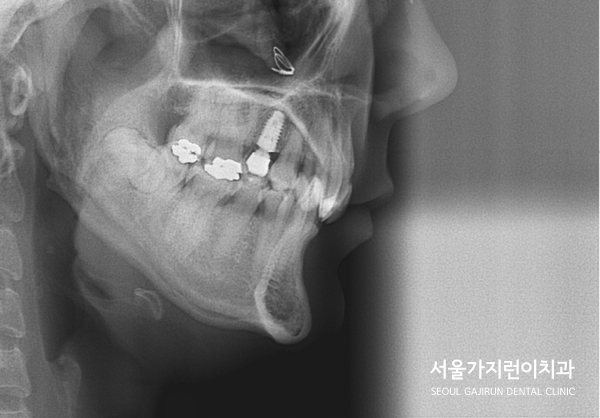

환자분의 경우 과개교합에 해당하셨는데요.

과개교합의 경우 윗니가 아랫니를 비정상적으로 덮고 있는 교합을 말합니다.

아랫니가 윗니를 덮는 경우는 주걱턱으로 많이 알고 있지만 반대의 경우 생각보다 많이 계신데요.

상악 앞니가 하악 앞니를 누르고 있었기 때문에 상당한 통증도 호소한 케이스였습니다.

게다가 윗니에 임플란트까지 있는 케이스, 아랫니에는 사랑니도 있었는데요.

엑스레이 상으로도 중첩되어있던 교합이 정상교합으로 돌아온 것을 확인할 수 있었습니다.